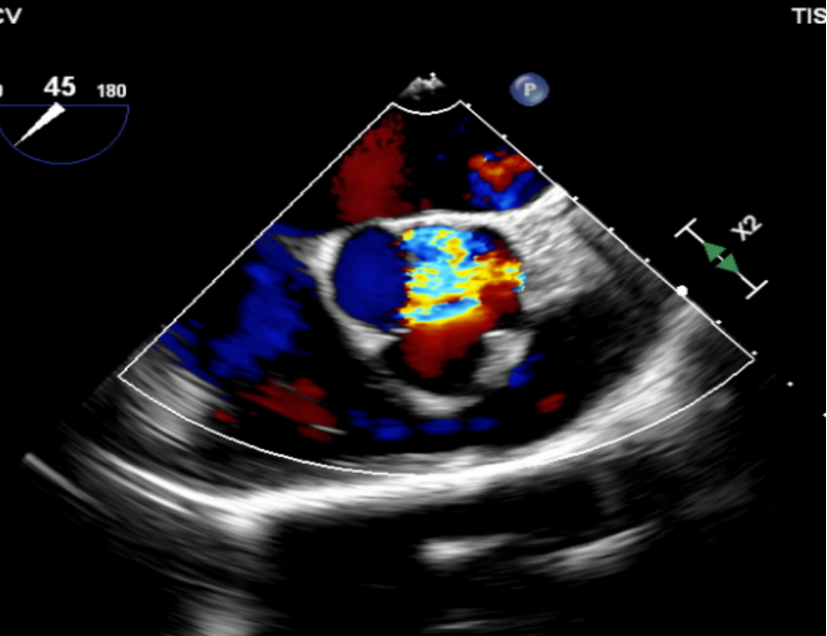

左室长轴切面可见流出道结构良好,短轴切面可见主动脉瓣大量反流。

(流出道结构观察)

(短轴切面观察)